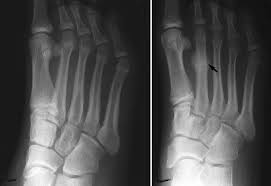

The metatarsal bones are the long bones in your foot that connect your ankle to your toes.

If you think you may have a stress fracture in your foot or ankle, the most important thing to do is to immediately stop all activities that cause pain. The pain tends to come on during exercise and eases off braces: This fracture walking boot is a quality boot at a good price. In the foot, the navicular stress fracture is the most common but they can occur in a number of bones in the foot and heel. Stress fractures occur most often in the second and third metatarsals in the foot, which are thinner (and often longer) than the adjacent first metatarsal.

Stress Fractures from www.rchsd.org Stress fractures of the metatarsal bones (march fractures) usually occur in runners who too quickly change the intensity or length of workouts and in poorly conditioned people who walk long distances carrying a load (for example, newly recruited soldiers). Before i went to the doctor, i shrugged it off as shin splints, and tried icing it down when i finished running. One way this happens is when you tack on too many miles too quickly. The solid bones and the pliable ligaments flex the foot to disperse the forces generated with walking, running, and jumping. A stress fracture foot problem usually starts off with mild pain and gradually gets worse. In severe cases, you may need a. Stress injuries can be found in the shin bone, foot, heel, hip and lower back. In this the bone breaks but generally does not shift the position.